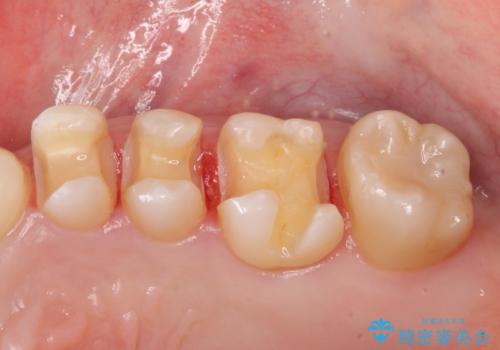

3本仮づめのまま放置 セラミックインレーへ

- 他院で治療途中で放置したところを治療したいとご来院されました。

仮づめはフロスもできないため、不潔になりやすく長期的には虫歯になりやすいです。

仮づめの状態でしたが、そこまで中は虫歯になっておらず、神経の治療も不要でした。